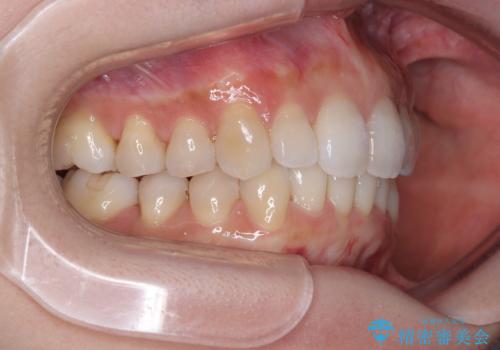

- デコボコと飛び出している前歯を気にして来院された患者様です。

歯列としてはインビザラインでもワイヤー矯正でも対応できるものでしたが、奥歯の咬み合わせを見た時に上顎がやや前方にあり、インビザライン単独では時間のかかってしまう可能性があるため、補助装置を治療当初に使用することで、インビザラインによる治療をスムーズに行えるように計画しました。

インビザラインは得意・不得意の差がはっきりとしているため、補助装置やワイヤー装置などをうまく活用することで、治療期間を短縮するとともに、より理想的な仕上がりを達成することができます。